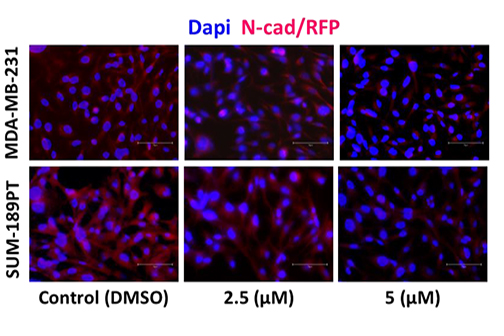

LSU Health Research Suggests A New Approach For Treatment-Resistant Breast Cancers

A collaborative study between LSU Health New Orleans School of Medicine, the University of Rochester and Cellestia Biotech AG, a biopharmaceutical company headquartered in Basel, Switzerland, provides compelling evidence that combining an investigational oral drug with standard-of-care medications reverts hormone resistance and increases Rx effectiveness in experimental models of estrogen-receptor positive (ER+) and triple-negative breast cancers (TNBC), respectively. More

LSU Health Research Finds New Drug Target for Triple-Negative Breast Cancer

Research led by Dr. Suresh Alahari, Professor of Biochemistry at LSU Health New Orleans’ Schools of Medicine and Graduate Studies, reports a combination of a novel small inhibitory molecule and an FDA-approved chemotherapy drug suppresses the growth of triple-negative breast cancer cells synergistically. More

LSU Health Research Suggests Novel Combination Therapy for Triple-Negative Breast Cancer

Research led by Suresh Alahari, PhD, Professor of Biochemistry at LSU Health New Orleans schools of Medicine and Graduate Studies, suggests a combination of drugs already approved by the FDA for other cancers may be effective in treating chemo-resistant triple-negative breast cancer. More